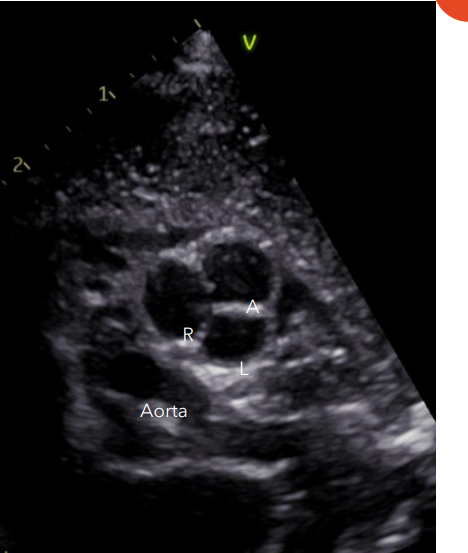

The Pulmonary Valve • how many and describe the shaped cusps:, and name each one

3 half moon shaped cusps: •

Anterior cusp • Left cusp • Right cusp

Typically we only visualize the right and anterior cusps during an echocardiogram in PSAX

The Pulmonic Valve is obtained in what view, with what o’clock rotation of the probe?

Obtained in PSAX with a 4-5 o’clock rotation of the probe